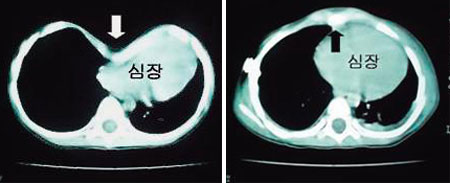

(¿ÞÂʺÎÅÍ) ¿À¸ñ°¡½¿ ¼ö¼ú Àü, ¿À¸ñ°¡½¿ ¼ö¼ú ÈÄ